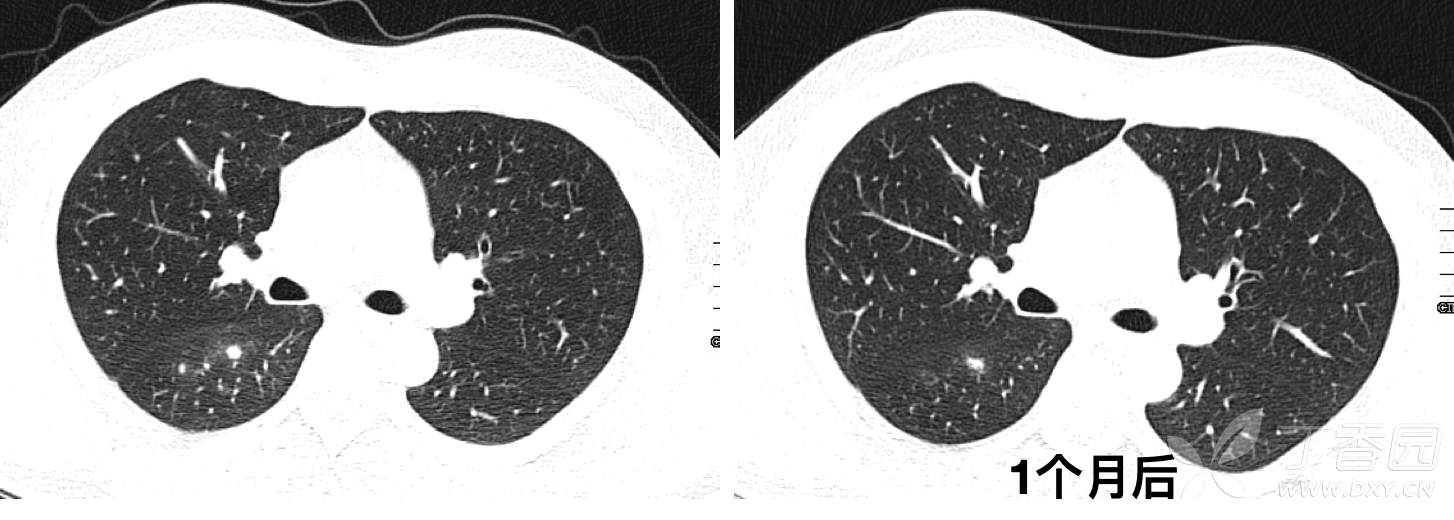

CT发现右肺多发结节影,初步诊断为肺炎,予莫西沙星口服治疗2周,1个月后复查CT如下: